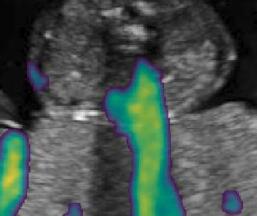

Fig. 6 compares the shadow confidence maps of the state-of-the-art methods and the proposed methods. RW and have the same parameters as used for Table I. The shadow confidence maps of the baseline, the proposed method and the proposedAG method are generated directly from input shadow images by confidence estimation networks. Overall, the proposed method and the proposedAG method achieve more visually reasonable shadow confidence estimation than the baseline and the state-of-the-art on different anatomical structures shown in Fig. 6. The proposed method and the proposedAG method are able to highlight multiple shadow regions while the RW algorithm shows limitations for most cases, especially for disjoint shadow regions.

Row I in Fig. 6 shows a fetal brain image from . The confidence estimation of shadow regions from the baseline, the proposed method and the proposedAG method are similarly accurate since we use fetal brain images to train the confidence estimation networks in these three methods. These outperform [16] and [22]. Rows (II-IV) in Fig. 6 show shadow confidence maps of non-brain anatomy from , including lips, abdominal and cardiac. The baseline failed on unseen data during inference. However, the proposed methods are able to generate accurate shadow confidence maps because of the generalized shadow features obtained by the shadow-seg module. Furthermore, the “Lips” example shows that our method is capable of detecting weaker shadow regions that have not been annotated in manual segmentation. This indicates that the confidence estimation network has learned general properties of shadow regions.

-D Alternative Examples of Shadow Confidence Estimation

We show an alternative group of examples for the confidence estimation of shadow regions (shown in Fig. 14). These examples include fetal brain from , and cardiac, lips, kidney from . Similar to the Fig. 6 in the main paper, Fig. 14 shows that the baseline fails to handle unseen data while the proposed method and the proposedAG method are able to predict pixel-wise confidence of multiple shadow regions. These examples demonstrate that the shadow-seg module is able to generalize the shadow representation and transfer shadow representation from the shadow/shadow-free classification task to a confidence estimation task.